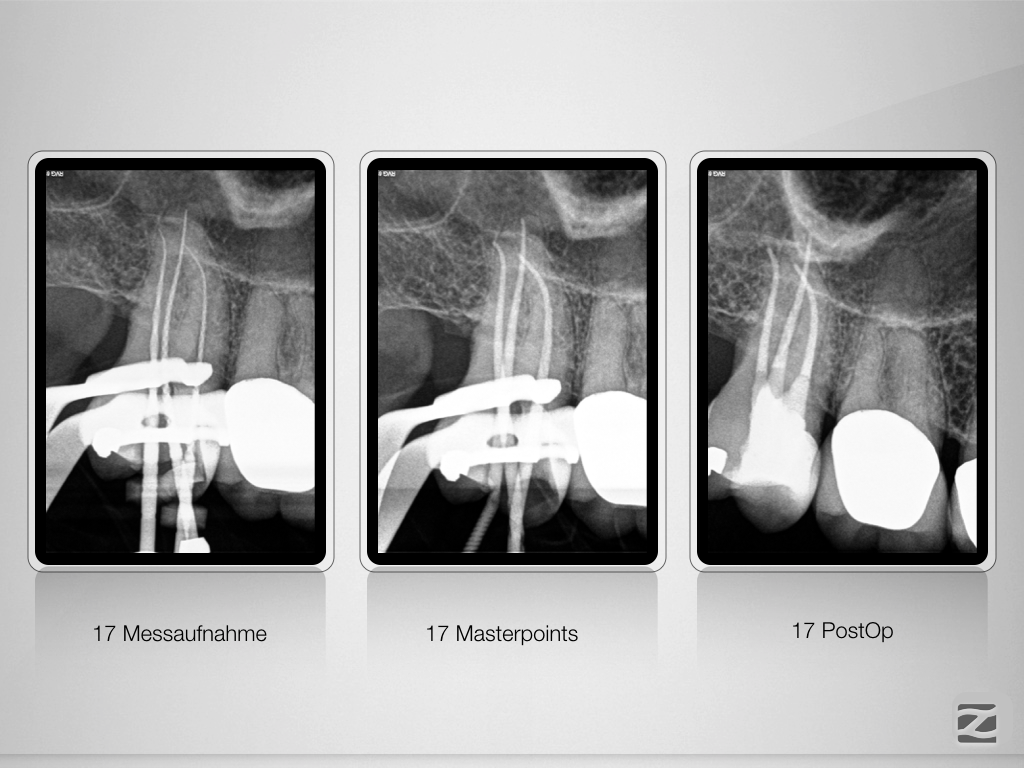

47D, 17D.010

Allerweltsfälle 2 & 3